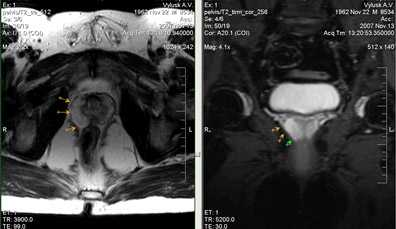

а) Т2-аксиальное изображение б) Т2-корональное изображение.

Муж., 62 лет. Верифицированный рак простаты. В заднее-латеральных отделах периферической зоны левой доли железы (на границе центральной и апикальной частей простаты) визуализируется участок патологически пониженного МР-сигнала. Целостной капсулы железы сохранена (стадия Т2а).

Т2-ВИ, аксиальная плоскость. Са (саncer)-мелкий очаг патологически пониженного МР-сигнала.

Определяется участок патологически пониженного МР-сигнала в периферической зоне левой доли простаты (центральная часть железы). При этом визуализируется нарушение целостности капсулы предстательной железы (Т3а стадия).

а)Т2-cor б)Т2-tra в) Т1FS din+С

Определяется больших размеров опухоль правой доли предстательной железы с инвазией ее капсулы, распространением на парапростатическую клетчатку (стрелки). При внутривенном динамическом контрастировании (в) в артериальную фазу определяется выраженное, диффузно неоднородное усиление ткани опухоли.

а) Т2-аксиальное изображение б) Т2-корональное изображение

Определяется опухоль левой доли предстательное железы с признаками распространение на основание левого семенного пузырька (стрелки, б).